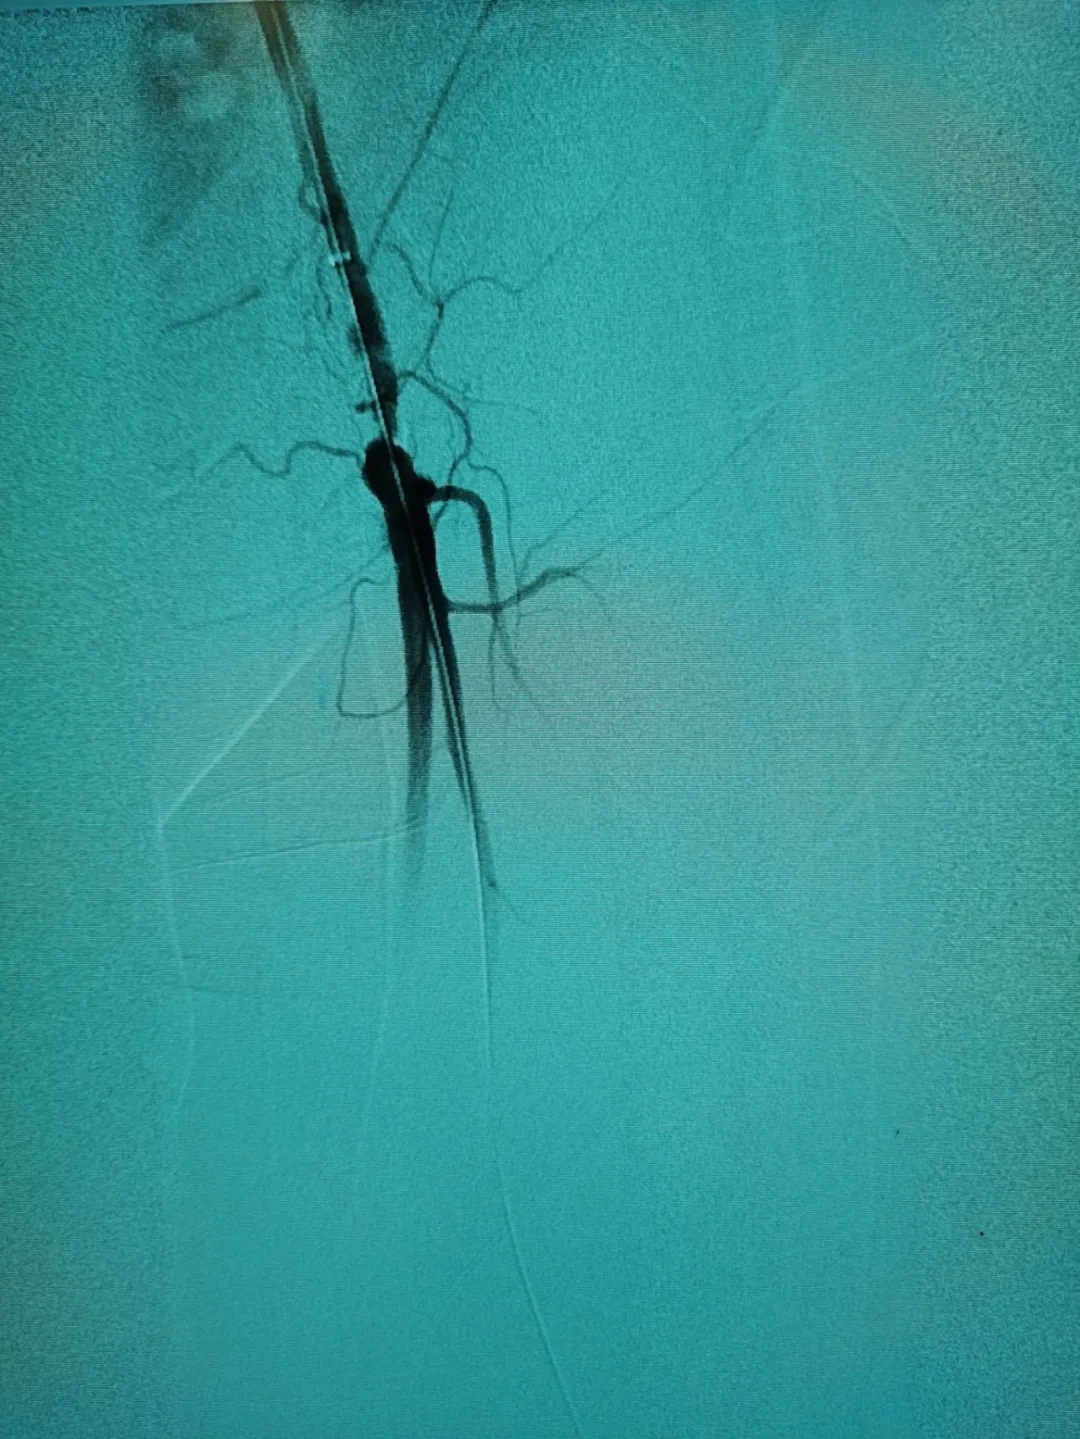

3月中旬,家人帶其到我院神經(jīng)外科治療。“根據(jù)患者的描述,是非常典型的間歇性跛行,我們給他做了雙下肢的血管造影,進一步證實了這一點。”施宏飛主任說,通過影像學(xué)檢查發(fā)現(xiàn),患者血管存在嚴(yán)重鈣化的斑塊,且左側(cè)股總動脈下段中重度狹窄,左側(cè)股淺動脈下段重度狹窄。

經(jīng)過周密的術(shù)前討論,施宏飛主任在團隊專家王明義副主任醫(yī)師及介入手術(shù)室醫(yī)護人員的配合下為患者實施了左側(cè)下肢動脈斑塊旋切+藥物球囊擴張術(shù)。

術(shù)中,醫(yī)生通過股動脈穿刺,利用專用器械進行血管腔內(nèi)斑塊切除,“就像電動刮胡刀一樣,我們用這個工具把堵塞在血管里的‘垃圾’一點一點刮下來,然后再取出來。”施宏飛主任說,為了保證“一網(wǎng)打盡”,他們還事先導(dǎo)入了遠端“保護傘”,如果旋切過程中切下的小斑塊掉落下去,也會被這個“保護傘”完全兜住,最后連同“保護傘”一起收起來,以杜絕后患。

將這些動脈斑塊清除之后,又利用球囊為患者進行血管擴張,病變血管形態(tài)改善良好,可以清楚看到血管內(nèi)大量增生內(nèi)膜被旋切出來,取出遠端保護傘可以看見大量過濾的內(nèi)膜組織。